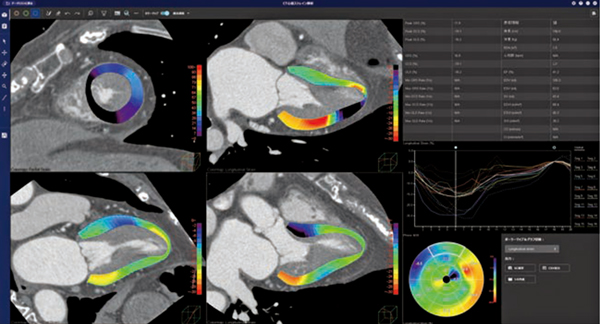

「CT心筋ストレイン解析」は,2024年に発表した「PhyZio/dynamics2.0」という弊社独自の動態解析技術を用いて開発を行っている。MR心筋ストレイン解析と同様に,4D-CTのデータを開くと,短軸像および長軸像(2ch,3ch,4ch)のすべての断面で左室心筋内壁と外壁の輪郭線を自動抽出してボクセルトラッキングを行い,心筋のストレイン解析を行う(図4)。

MRIは,循環器領域の診断において重要な検査である一方,検査時間の長さや撮像禁忌などの課題もある。CTは,国内においてMRIに比べアクセスが良く,撮影も短時間で行えるため,その実用性の高さからストレイン解析においてもCTの活用が期待される。

図4 CT心筋ストレイン解析(W.I.P.)